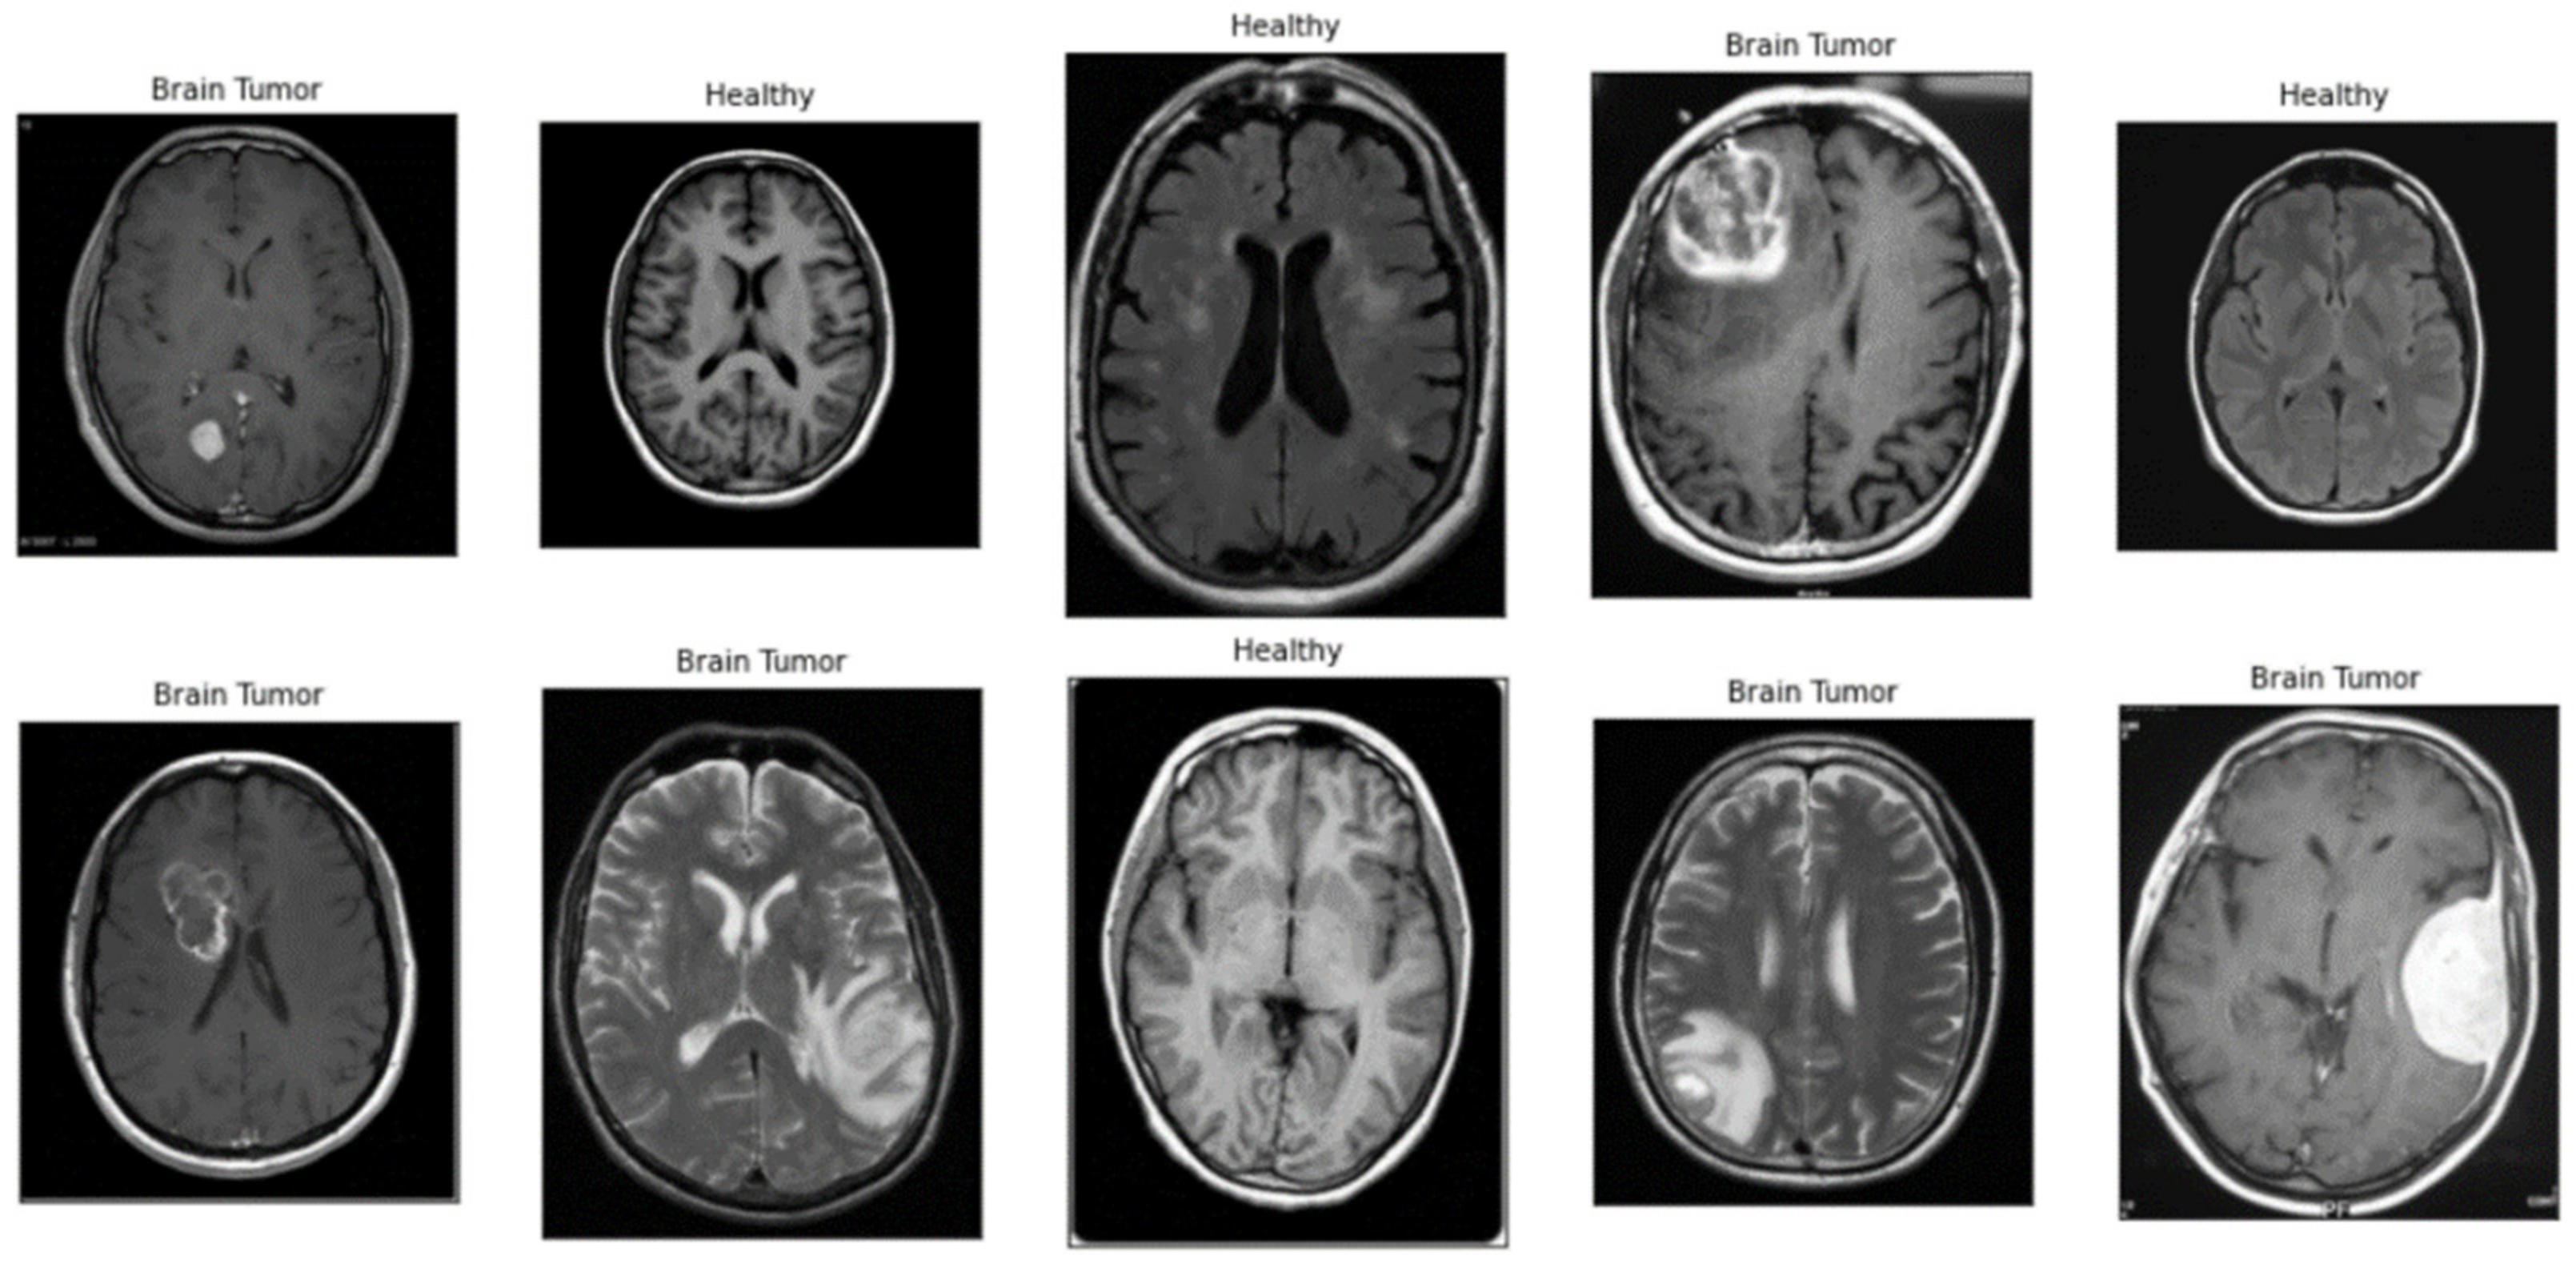

2. Proposed CNN Model in Brain Tumour Dataset